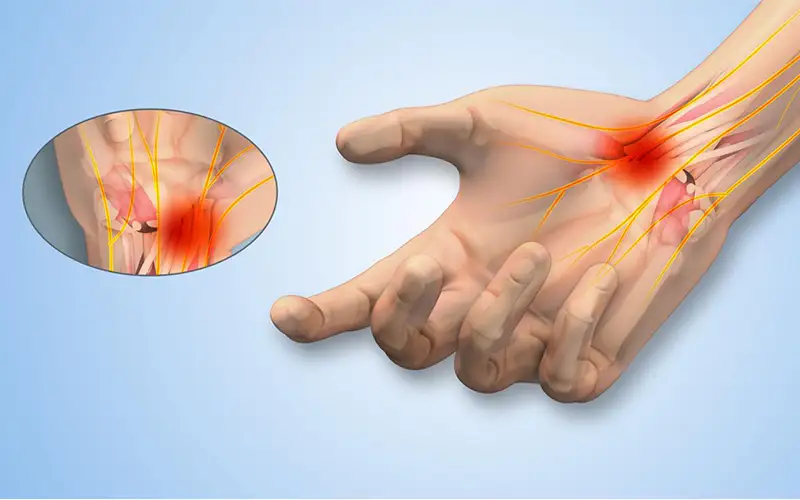

سندروم تونل کارپال (تونل مچ دست)

سندروم تونل کارپال (Carpal Tunnel Syndrome) یکی از شایعترین اختلالات عصبی دست است که در ا...